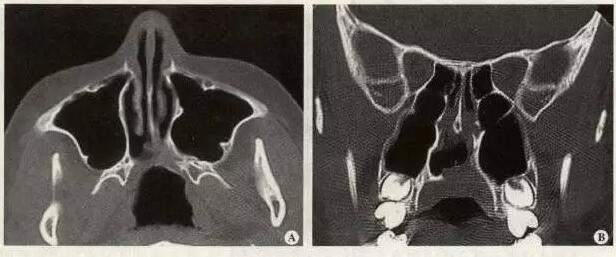

先天性后鼻孔闭锁是一种很少见的先天性畸形,发病率约为1/8000,单侧后鼻孔闭锁多见,双侧完全性闭锁较为罕见,大部分闭锁为膜性或混合性,骨性闭锁约为30%。先天性后鼻孔闭锁的致畸学说很多,目前比较公认的是在胚胎发育过程中鼻颊膜或颊咽膜遗留,或后鼻孔被上皮团块阻塞导致的。根据阻塞的鼻腔可分为单侧和双侧二种,单侧性后鼻孔闭锁一般症状较轻,主要为单侧鼻塞、鼻腔分泌物较多,家长常常不会很早发现;双侧后鼻孔完全性闭锁症状较重,出生时即出现阵发性发绀,吮奶时呼吸困难、憋气,张口啼哭时症状缓解,鼻腔分泌物较多,常伴有肺部感染;这些新生儿常常因为伴有肺部感染而入住新生儿监护室。后鼻孔闭锁诊断一般还是比较容易的,常见的诊断方法有用细的导尿管导入鼻腔,观察其是否能下达到咽部,或注少许美蓝于鼻腔内,检查咽部是否有蓝色;这些都是最为简单和直接的诊断方法,但不能判断闭锁的部位、性质、程度及于周围组织的关系,CT检查在诊断先天性后鼻孔闭锁中有重要的临床意义,可以准确判断闭锁的性质、部位及程度,CT的检查对手术医生来说,可以正确判断手术时机,对手术方法的选择具有重要的指导意义。